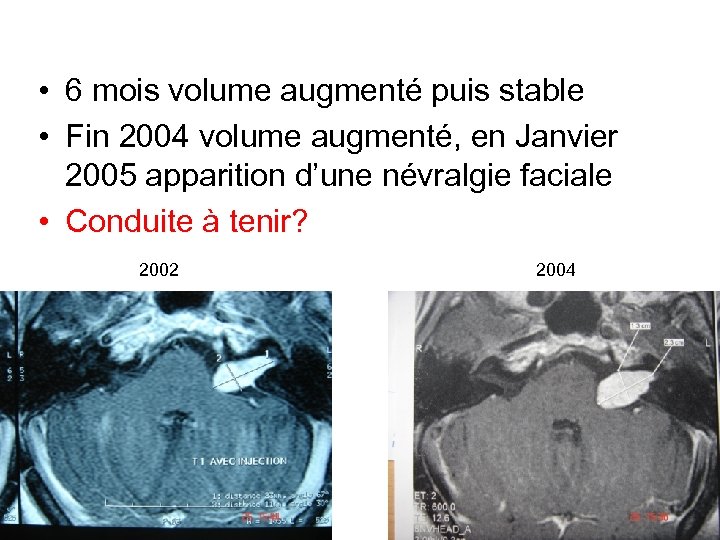

• 6 mois volume augmenté puis stable • Fin 2004 volume augmenté, en Janvier 2005 apparition d’une névralgie faciale • Conduite à tenir? 2002 2004

• 6 mois volume augmenté puis stable • Fin 2004 volume augmenté, en Janvier 2005 apparition d’une névralgie faciale • Conduite à tenir? 2002 2004

• 6 mois volume augmenté puis stable • Fin 2004 volume augmenté, en Janvier 2005 apparition d’une névralgie faciale • Conduite à tenir?

• 6 mois volume augmenté puis stable • Fin 2004 volume augmenté, en Janvier 2005 apparition d’une névralgie faciale • Conduite à tenir?

Conduite à tenir? • Opérée par voie trans labyrinthique • Conservation du facial grade 1

Conduite à tenir? • Opérée par voie trans labyrinthique • Conservation du facial grade 1